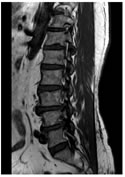

CASE 1

LUMBARIZED S1 VERTEBRA IS NOTED

T1W PARASAGITTAL IMAGE SHOWING MODERATE THECAL SAC STENOSIS ON THE LEFT (OBLITERATION OF FAT PLANE) ABUTTING THE L5 EXITING NERVE ROOT AT L5-S1 LEVEL

T1W AXIAL IMAGE SHOWING SEVERE THECAL SAC STENOSIS (<75 mm2) AT L5-S1 LEVEL DUE TO DIFFUSE DISC BULGE AND LIGAEMETNUM FLAVUM HYPERTROPHY AND FACETAL ARTHROPATHY